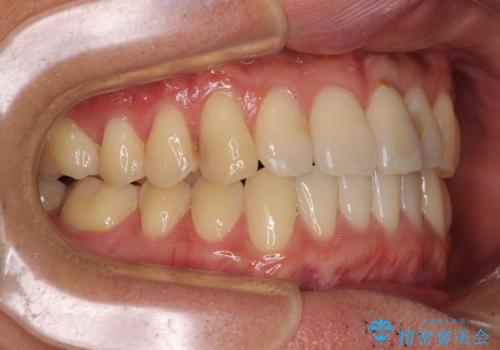

気になる前歯のデコボコをインビザラインで解消

- 前歯のデコボコを気にして来院された患者様です。

主に下顎歯列全体の後方移動とIPR(歯と歯の間を削る)によってデコボコが解消するように設計し、インビザラインにより治療を行うこととしました。

インビザライン矯正特有の、治療後半で前歯のみが強く接触する症状が発現し、咬み合わせ改善に期間を要することとなりました。